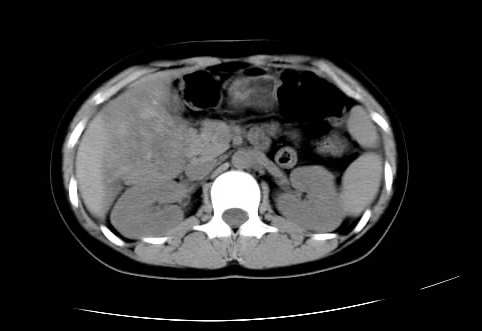

女 16岁  右上腹痛一天,无其他不适

肿块最大径位于十二指肠降段与水平段移行处,并且与肝脏压迹呈“0”形征,可以考虑位于肝外并与胃肠道关系紧密,考虑胃肠道间质瘤(gist)可能较大,须除外神经节起源肿瘤。

肿块与十二指肠关系密切,支持间质瘤诊断.肝脏与结肠均为受压改变.

我坚决反对您的观点,该病例定位:横结肠肝曲与升结肠之间的肠系膜及部分肠壁。请看下图:

病灶巨大,少部分向肠腔内生长,大部分向长腔外生长。其密度不均匀,增强显示明显不均匀强化,并见有大片状始终不强化的不规则坏死液化区。虽然病灶中上部形态尚可,病人又如此年轻,但中下部形态、密度、强化特点强烈提示为恶性病灶。综上,我考虑本病例为:恶性胃肠道间质瘤。